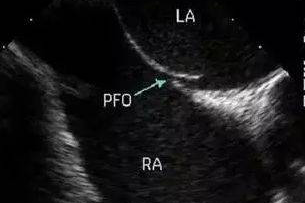

经食管超声心动图检查(TEE)是将食道超声探头置于食管或胃底,从心脏后方探查心脏及大血管解剖结构和血流信息的影像诊断技术。近年来,经食管超声心动图检查已经在临床得到广泛应用,对心血管疾病的诊断、治疗以及疗效评价产生了巨大影响,逐渐成为心血管疾病的主要诊疗方法和金标准。

您好!与普通的胸部超声相比,TEE探头直接贴近心脏后方扫查,明显缩短了探头与心脏及其周围大血管的距离,同时也不受肋骨、胸骨、肺及皮下脂肪的干扰,因此图像更清晰,尤其对于心脏后部结构,如对房间隔、主动脉瓣、二尖瓣、左心耳及胸主动脉等结构的显示更具有优势。